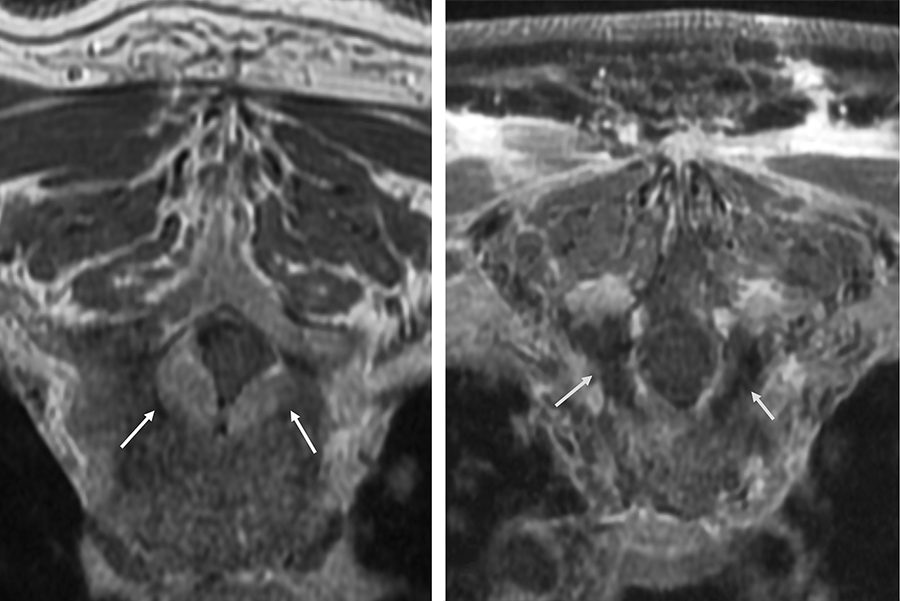

El estudio retrospectivo—dirigido por la Dra. Audree Tadros y el Dr. Henry Kuerer, Ph.D., fellow y profesor, respectivamente, del Departamento de Oncología Quirúrgica de Mama—fue realizado para aclarar los beneficios de la radioterapia en la prevención de la recurrencia locorregional en pacientes con DCIS luego de la cirugía de mama conservadora con márgenes quirúrgicos negativos inferiores a 2 mm (es decir, con menos de 2 mm de tejido libre circundante al tumor en la muestra extirpada). La estrategia de tratamiento óptima para tales pacientes no está establecida. “Muchos grupos multidisciplinarios actualmente utilizan el margen de 2 mm como indicación absoluta para la segunda cirugía”, dijo el Dr. Kuerer.

Los Dres. Tadros y Kuerer y sus colegas observaron los registros de casi 1,500 pacientes con DCIS que se sometieron a la cirugía de mama conservadora en el MD Anderson entre 1996 y 2010. Algunas pacientes habían recibido radioterapia posteriormente a la cirugía, en tanto que otras no lo habían hecho; ninguna se había hecho una segunda cirugía. Los investigadores compararon las tasas de recurrencia locorregional de las pacientes con márgenes quirúrgicos negativos superiores o iguales a 2 mm y de aquellas con márgenes negativos inferiores a 2 mm en el grupo que había recibido radiación y en el que no la había recibido.